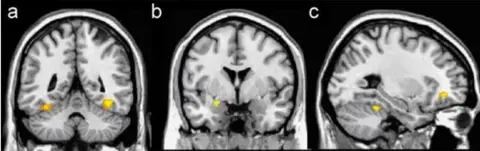

Jay van Bavel/Dominic PackerBy using functional magnetic resonance imaging - like the MRI scans doctors use to detect brain injury, but tracking changes in blood flow - we monitored activity in regions of the brain that indicate emotions or perceptions.

The brain data, in particular, suggested that when people understood themselves as part of a common group, they began to see one another as individuals.